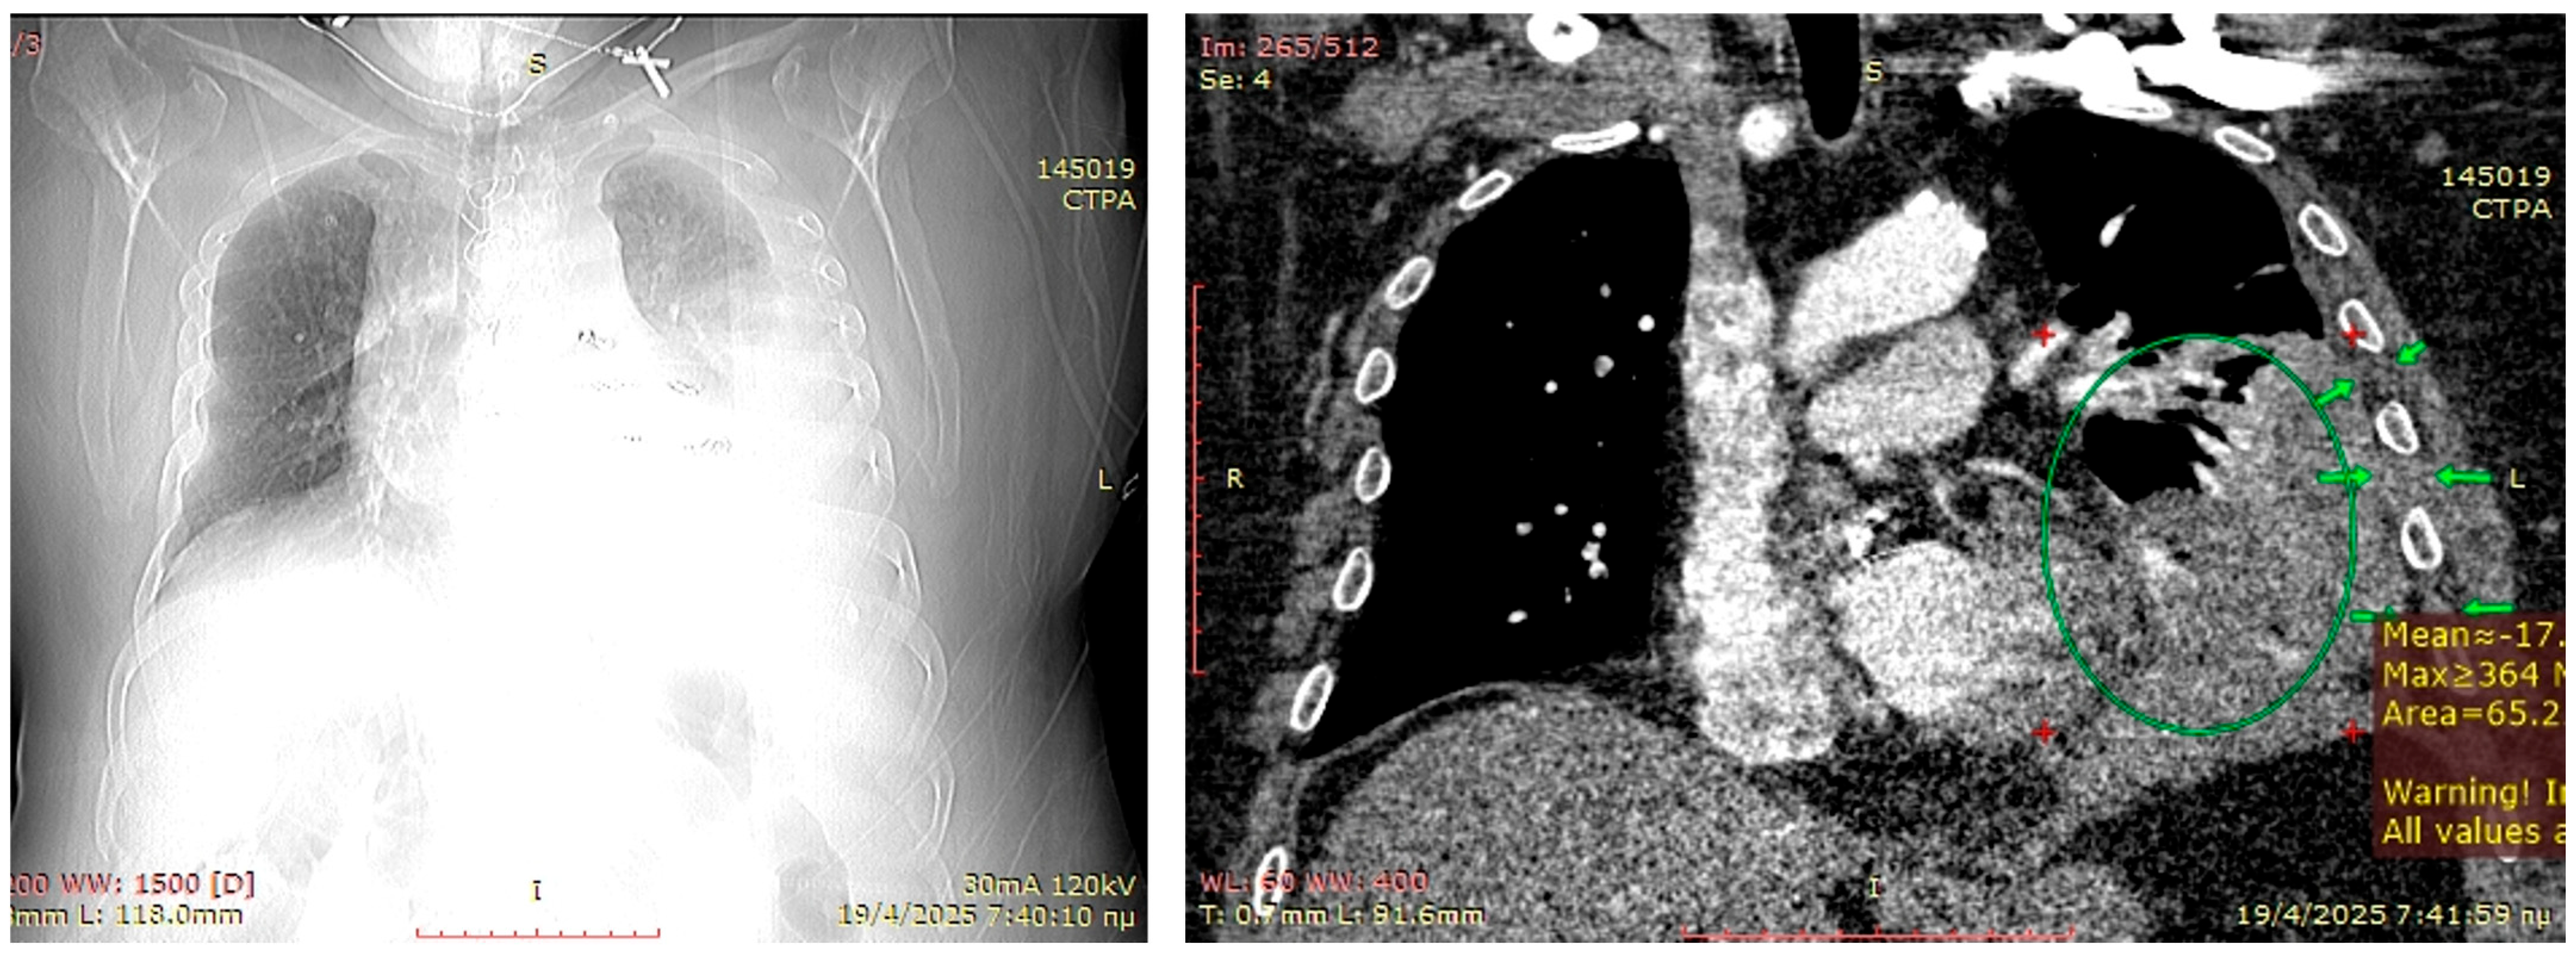

3.3. Patient 3

A 55-year-old male obese (BMI > 35) smoker developed pneumonia, which was partially treated with successive antibiotic courses, eventually leading to antibiotic resistance, and a parapneumonic pleural effusion treated with an ultrasound guided small-bore Seldinger-type pleural catheter. Upon spending three weeks in the respiratory ward, he developed hemoptysis while receiving low-molecular-weight heparin for treatment of segmental pulmonary emboli. The hemoptysis decreased at 2 days after heparin cessation and tranexamic acid administration; however, his respiratory physiology remained suboptimal, raising concerns either for pulmonary embolism or parenchymal necrosis. A CT pulmonary angiogram performed for excluding new pulmonary embolism revealed left lower lobe necrosis with contrast leakage in the pleural cavity (Figure 4). A small ruptured abscess could not be excluded. On acute basis, the patient underwent an exploratory left lower antero-lateral thoracotomy at the 7th intercostal space. The pleural cavity had blood clots present, and the lower lobe was necrotic on the lateral segment. Selective bronchial closure for single lung ventilation was insufficient to maintain acceptable O2 saturations, precluding our initial plan for a salvage lower lobectomy. A wide-wedge resection was performed on the necrotic lung, and the long stapling line was reinforced with a Serratus anterior flap. Decortication was partially performed with eventual suboptimal lung expansion. To anticipate a chronic infected space, a muscular ‘blanket’ of the intercostal muscles from ribs 5–8 and the underlying thick parietal pleura was prepared and with the serratus anterior flap was secured in the cavity. Two chest drains were inserted, and a smaller bore drain was inserted in the subcutaneous space. The patient recovered from pleural sepsis, regaining almost complete lung expansion. Within 45 days, he achieved full recovery and returned to his previous physically demanding occupation.

Figure 4. Preoperative planning CT-scan. Although the topogram similar to a standard antero-posterior chest x-ray shows the approximate extent of a parapneumonic effusion and an estimation of the location, it is of little practical value compared to a CT-scan. The right coronal view of the CT-scan is of much higher value to recognize the severe parenchymal infiltration (green circle) which prohibits decortication and describes the thickness of the chest wall to estimate if a Sawamura thoracoplasty by soft-tissue mobilization can be attained (green arrows).